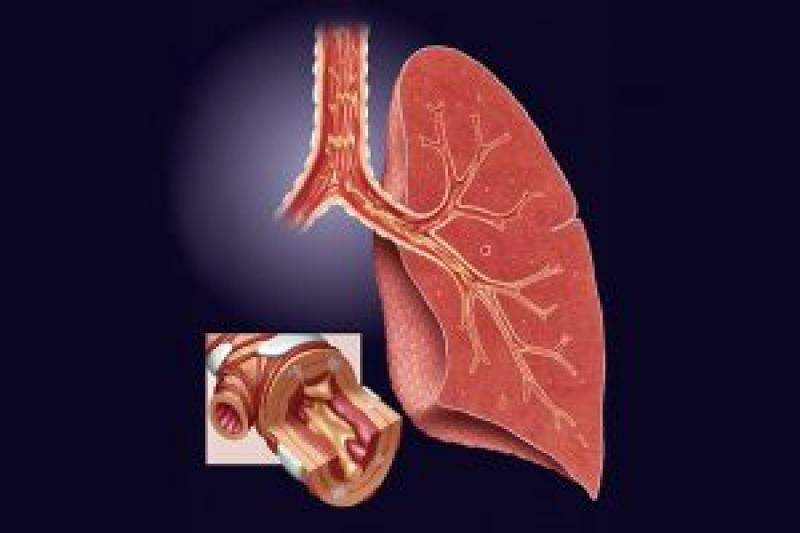

The infection in the airways of lungs (bronchi) is known as bronchitis, which is of two types, namely, acute and chronic bronchitis. Acute bronchitis resolves within two to three weeks while chronic bronchitis is the condition when a cough exists for at least three months and at least two years in a row. Smoking, viruses such as flu and bacteria, inhalation of irritating fumes or dust are the major causes of chronic bronchitis. Chest X-ray, sputum tests, and pulmonary function tests are various tests performed for the diagnosis of acute as well as chronic bronchitis.